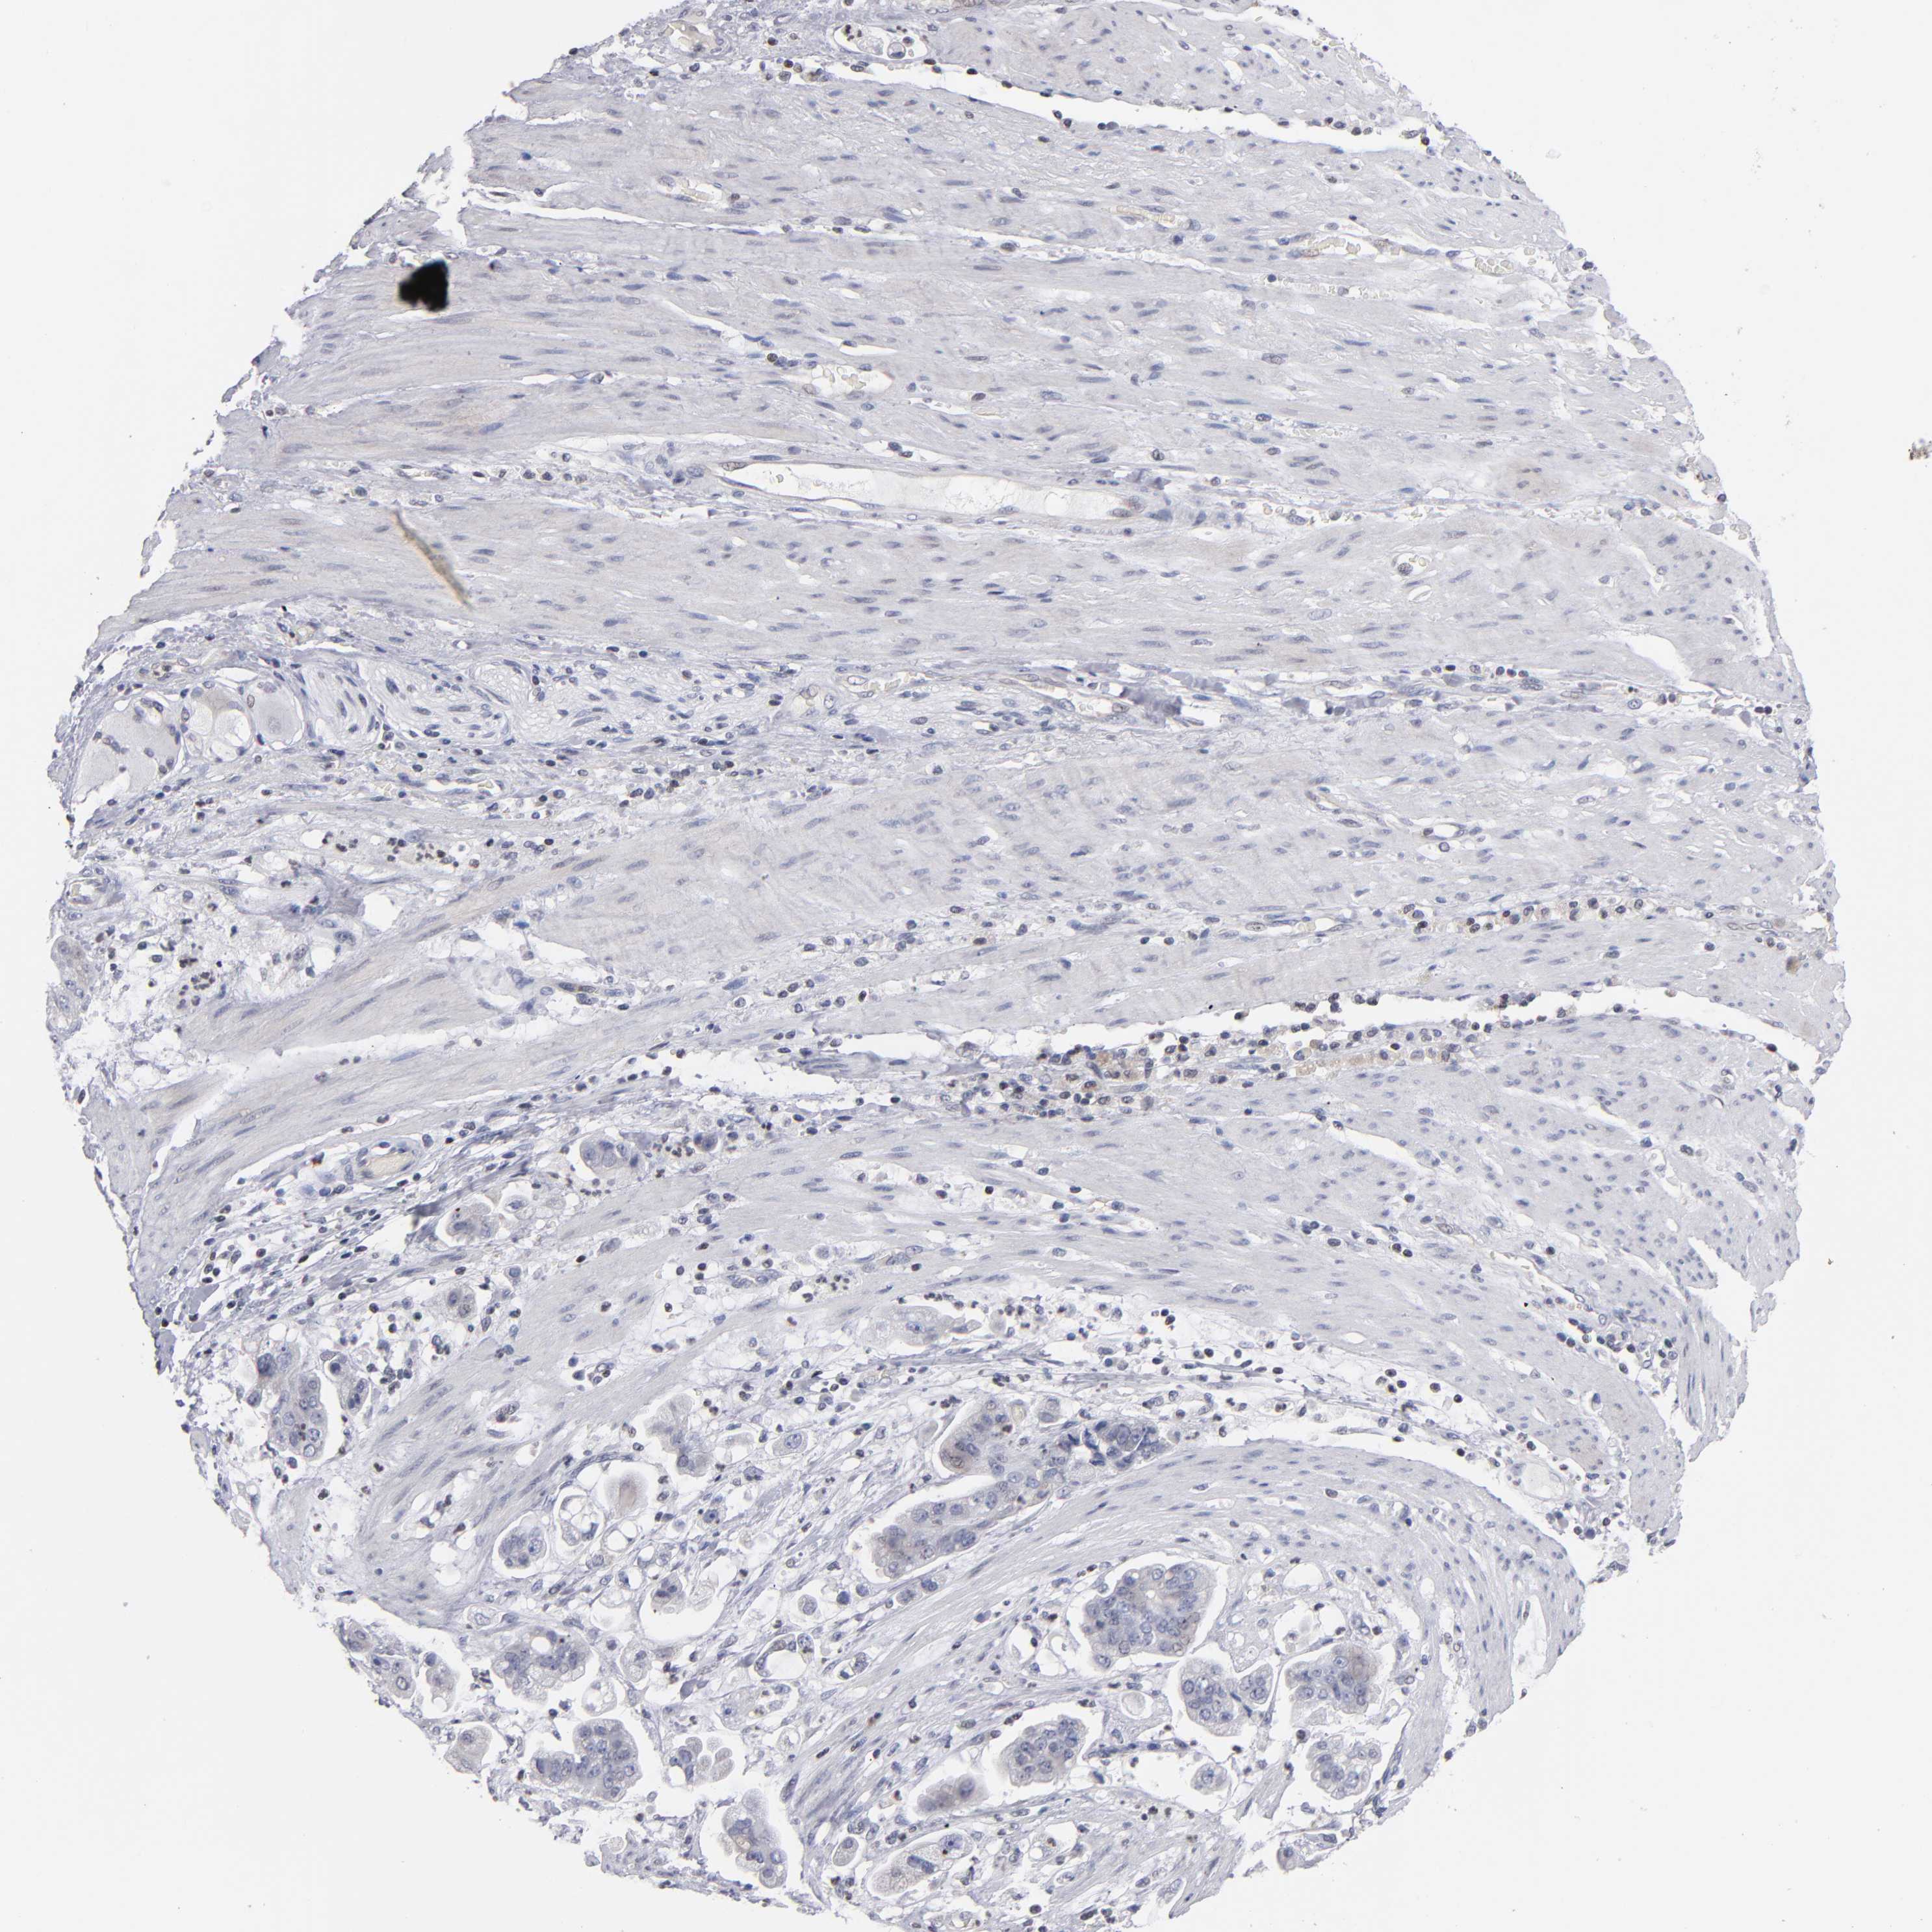

STOMACH CANCER - Protein expressioni

A mouse-over function shows sample information and annotation data. Click on an image to view it in a full screen mode. Samples can be filtered based on level of antibody staining by selecting one or several of the following categories: high, medium, low and not detected. The assay and annotation is described here.

Note that samples used for immunohistochemistry by the Human Protein Atlas do not correspond to samples in the TCGA dataset.

Antibody stainingi

Antibody staining in the annotated cell types in the current human tissue is reported as not detected, low, medium, or high, based on conventional immunohistochemistry profiling in selected tissues. This score is based on the combination of the staining intensity and fraction of stained cells.

Each image is clickable and will lead to virtual microscopy that enables deeper exploration of all samples and also displays staining intensity scores, fraction scores and subcellular localization as well as patient and tissue information for each sample.

Antibody HPA001874

Staining

High

Medium

Low

Not detected

Intensity

Strong

Moderate

Weak

Negative

Quantity

>75%

75%-25%

<25%

None

Location

Nuclear

Cytoplasmic/membranous

Cytoplasmic/membranous,nuclear

Adenocarcinoma, NOS

Adenocarcinoma, High grade